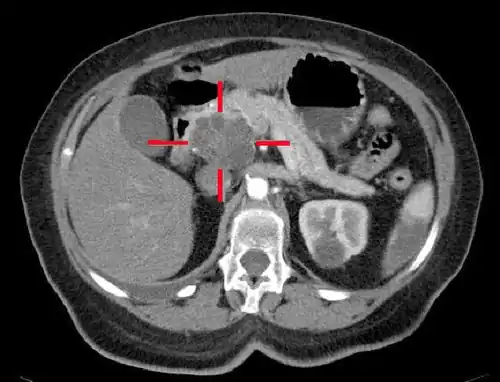

Imagerie

Elle vise à évaluer la taille et la localisation de la tumeur, et celles d'éventuelles métastases ganglionnaires, hépatiques, ou péritonéales.

On étudie également les rapports avec la veine porte.

Le scanner abdominal avec injection d'un produit de contraste iodé reste l'examen de référence. Il permet de mieux juger de l'extension locale et de l'existence de métastases, en particulier sur le foie et de juger ainsi de l'opérabilité[35].